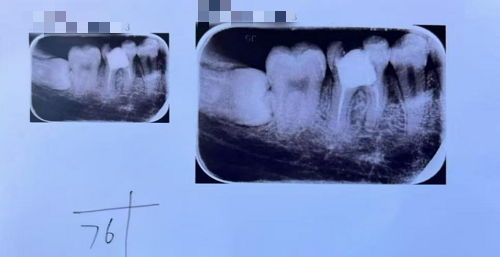

近日,彝良县人民医院口腔科收到了一份特别的礼物——一面印有“仁心生妙手 医术治牙疾”的锦旗,赠送者是不久前在此治疗牙齿的患者。同时,还撰写了一篇情真意切的“看牙记”,记录下自己在治疗期间的亲身经历,字里行间充满了对口腔科李治琴医生及其医疗团队的感激之情。 看牙记 这是一个关于看牙的亲身经历,一方面是想和大家分享一下看牙的经历,另一方面是为了感谢我的主治医生。 我是一个在校大学生,2022年右下后牙痛,医生说根尖炎,要做根管治疗,所以我做完根管治疗后牙不疼了。 但是好景不长,两年以后不小心咬硬物导致右下后牙折裂,于是到云南省口腔医院就诊,由于之前的根管治疗不够完善,且髓底似乎烂穿了,医生建议拔牙后做种植牙,那样的话至少得半年多才能修复好。 可是,我害怕拔牙、害怕种植手术,又过了三个月,牙齿劈裂更加严重了,牙冠只剩1/3,正好放假回家,到彝良县人民医院口腔科就诊,李治琴医生了解到我的需求后建议根管再治疗后打桩、烤瓷牙冠修复,抱着试试看的态度开始了治疗。 在李主任的细心处置下,根管再治疗非常成功。牙体修复完成仅仅三个星期,达到了意想不到的效果。 非常感谢李医生拯救了它没被拔除,并且为我节省许多了时间和费用。 Thank You 患者在“看牙记”中回忆,自己长期被牙齿疼痛困扰,严重影响了日常生活与饮食,之前的根管治疗不够完善,且髓底似乎烂穿了,需要拔牙后做种植牙,抱着试试看的心态来到彝良县人民医院口腔科后,李治琴医生耐心地为她进行了全面的细致的检查,详细讲解了牙齿治疗方案以及后续的注意事项,这让原本对看牙充满恐惧的她逐渐放下心来。 在整个治疗过程中,李治琴医生展现出了高超的专业技术。每一个操作步骤都精准、轻柔,最大程度减轻了患者的不适感。同时,医疗团队的护士们也给予了无微不至的关怀,时刻关注她的状态,及时给予安慰和鼓励。经过一段时间的精心治疗,患者的牙体修复了,笑容也重新绽放在脸上。 患者说道:为了表达内心的感激,她特意定制了锦旗,并写下“看牙记“希望通过自己的经历让更多人了解彝良县人民医院口腔科的优质医疗服务。 这面锦旗和“看牙记”不仅是患者对口腔科李治琴医生及其团队的高度认可,更是对彝良县人民医院“以患者为中心”服务理念的生动诠释。一直以来,我院始终致力于为患者提供专业、高效、贴心的医疗服务,不断提升医疗技术水平和服务质量。口腔科作为医院的重点科室之一,有经验丰富、技术精湛的上海帮扶口腔专家,配备了先进的医疗设备,能够为患者提供全方位的口腔诊疗服务。 欢迎关注“彝良县人民医院微信公众号”,方便您就医(提供预约挂号、缴费、检验检查报告查询、住院清单查询等服务)。